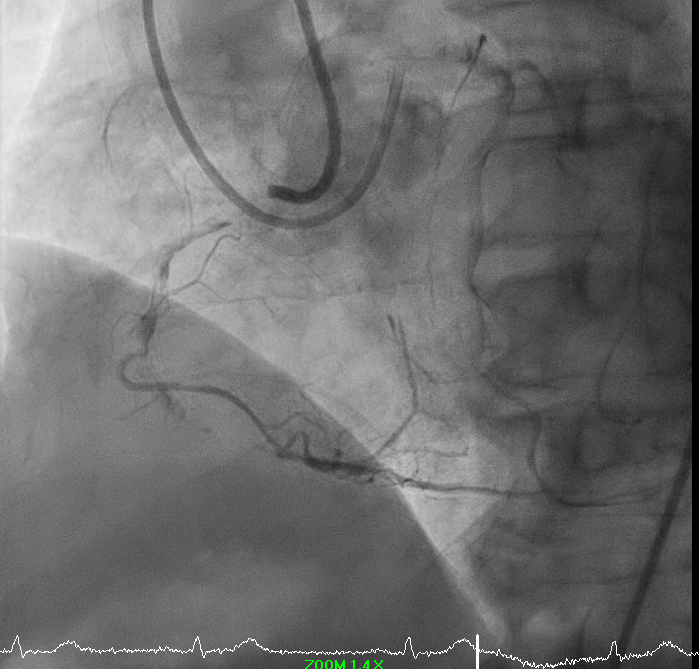

Predilation was challenging due to poor support. Initial 0.75 mm balloon could not pass; support was augmented with Sion Blue to RV branch. Subsequent predilation was performed sequentially with Zinrai 0.75 ¡¿ 4 mm, Ryureo 1.0 ¡¿ 5 mm, and NC balloon 2.0 ¡¿ 15 mm, achieving satisfactory antegrade flow. IVUS assessment demonstrated a distal vessel diameter of 2.5 mm, proximal/mid 3.5 mm, previous MSA 3.5 mm, and 360¡Æ proximal calcium. Additional predilation using Wedge 2.5 ¡¿ 15 mm (distal¡æproximal) and Scoreflex 3.0 ¡¿ 15 mm (mid¡æproximal) resulted in <30% recoil and no dissection. Post-IVUS, MSA improved from 3.5 ¡æ 4.8 mm.

A drug-coated balloon strategy was employed: Prevail 2.5 ¡¿ 30 mm @ 8 ATM ¡¿ 60s and Selution SLR 3.0 ¡¿ 35 mm @ 6 ATM ¡¿ 60s. Final angiography showed TIMI 3 flow with no residual dissection. The case highlights a complex RCA ISR-CTO managed successfully with a contemporary DCB-based, stent-less strategy guided by IVUS and meticulous lesion preparation.

12.avi

13.avi